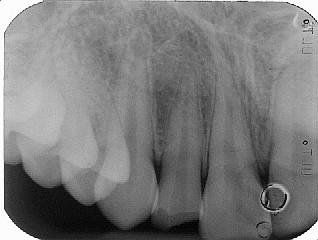

In caso di necrosi pulpare sull'apice del dente compare una lesione periapicale, il granuloma, un meccanismo di difesa dell'organismo volto al controllo dell'infezione batterica. In questo caso saranno necessarie una o più medicazioni canalari intermedie prima della completa otturazione dei canali.

Un corretto trattamento endodontico consente di eliminare l'infezione batterica dai canali radicolari e di risolvere il granuloma. Lavoriamo su tessuti umani, e può accadere che in alcune circostanze nonostante il trattamento canalare sia stato eseguito a regola d'arte, l'infezione batterica all'interno del canale permanga. In questi casi solitamente si ricorre ad un ritrattamento dei canali, e in ultima istanza è possibile ricorrere a un intervento di endodonzia chirurgica (si asporta chirurgicamente l'apice del dente e si otturano gli ultimi 3-4 millimetri del canale per via retrograda).